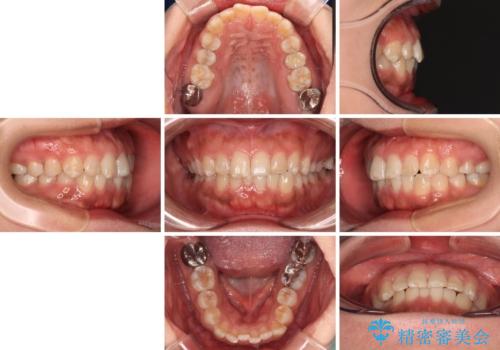

- 上下前歯の叢生を気にして来院された患者様です。

軽度な叢生であり、安価で短期間の治療を規模されていたため、インビザライン・モデレートを用いて矯正治療を行うこととしました。